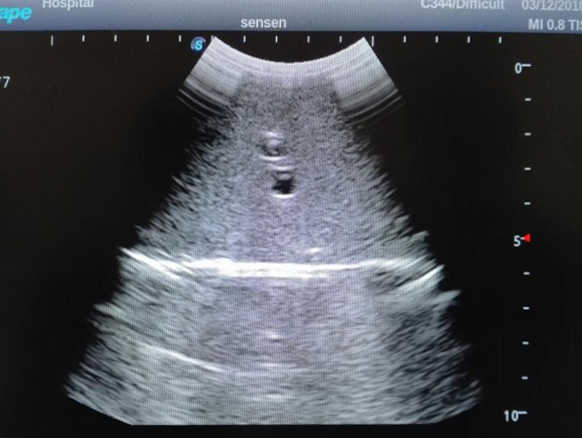

1)  Ideal for trainings like ultrasound-guided abdominocentesis with visible ascites flowing out, ultrasound-guided femoral artery & venous puncture

2)  High quality ultrasound image with clear structures like gallbladder, liver, intestines, arteries and veins etc.

3)  Compatible with all types of clinical ultrasound machines